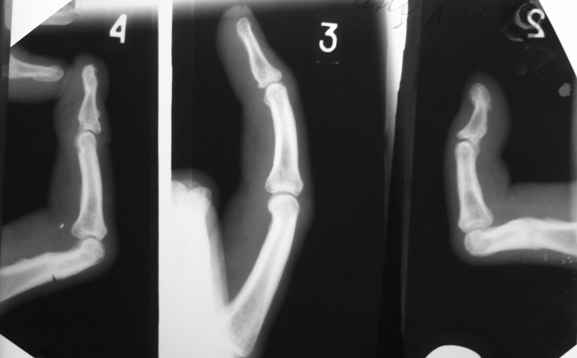

Ограничение движений одинаковое и активных и пассивных. Движения в указанном объеме свободные. Чем вызвано ограничение понять пока не можем. В боковой проекции досняли - получается, что подвывиха нет. Вопросов, в отношении того, что мешает  стало еще больше.

Имя     : Боковые ПМФС.JPG